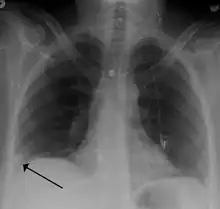

• Chest X-rays are often done on people with shortness of breath to help rule-out other causes, such as congestive heart failure and rib fracture. Chest X-rays in PE are rarely normal,[68] but usually lack signs that suggest the diagnosis of PE (for example, Westermark sign, Hampton's hump).

A Hampton hump in a person with a right lower lobe pulmonary embolism